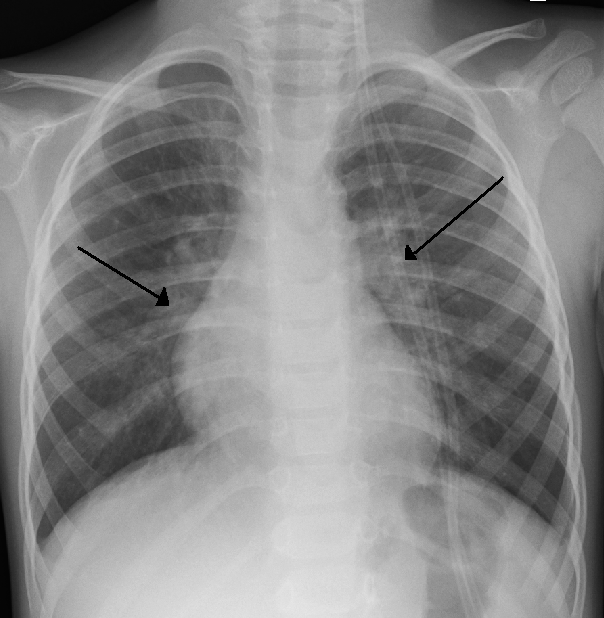

I malanni dell’inverno non sono solo raffreddore, influenza, bronchite ed otite. Nei bambini piccoli può essere frequente anche la bronchiolite, è un’infiammazione dei rami più sottili delle terminazioni bronchiali. L’agente infettivo più coinvolto (nel 75% circa dei casi) è il virus respiratorio sinciziale (VRS) ma anche altri virus possono esserne la causa (metapneumovirus, coronavirus, rinovirus, adenovirus, virus influenzali e parainfluenzali).

La fase di contagio dura tipicamente dai 6 ai 10 giorni ed interessa la zona dei bronchi e bronchioli innescando un processo infiammatorio, aumento della produzione di muco e ostruzione delle vie aeree con possibile comparsa di difficoltà respiratoria. Fattori che aumentano il rischio di maggiore gravità sono la prematurità, l’età del bambino (< 12 settimane), le cardiopatie congenite, la displasia broncopolmonare e le anomalie congenite delle vie aeree e le immunodeficienze.